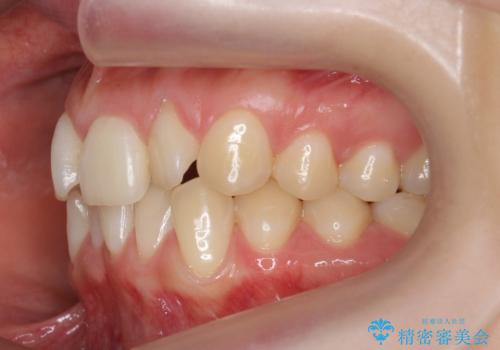

前歯がねじれている 奥歯を後ろに下げて歯を抜かずに並べました

- 前歯のねじれを主訴に来院。

前から2番目の歯がねじれて下の歯の内側に入っていました。

また、奥歯のかみ合わせが上の奥歯が若干前に並んでおり、それで前歯が入りきらずにねじれていました。

歯を抜かずに奥歯を後ろに下げてマウスピースで矯正しています。

上の奥歯を後ろに下げて前歯のねじれを治すスペースを確保しました。

奥歯を後ろに下げるために、矯正用インプラントを使用しています。